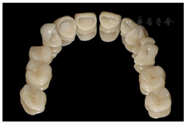

架

架临时修复体患者戴用无不适,上颌牙制作永久修复体,戴牙(图32,图33)。同样,对下颌牙进行牙体预备,取模,制作永久修复体,戴牙(图34,图35,图36,图37,图38,图39)。